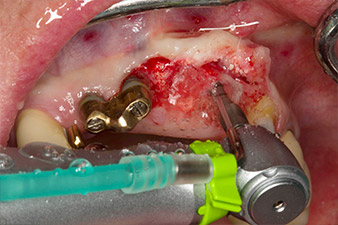

Motorized placement of the implant

Fig. 4: Motorized placement of the implant with the WS-75 L contra-angle handpiece at a ratio of 20:1 (programme P5).

In order to compensate for the periodontal bone loss and achieve an aesthetically pleasing result, the implantation was combined with guided bone regeneration (GBR) with xenogenic replacement material and a collagen membrane

(Fig. 5 and 6).